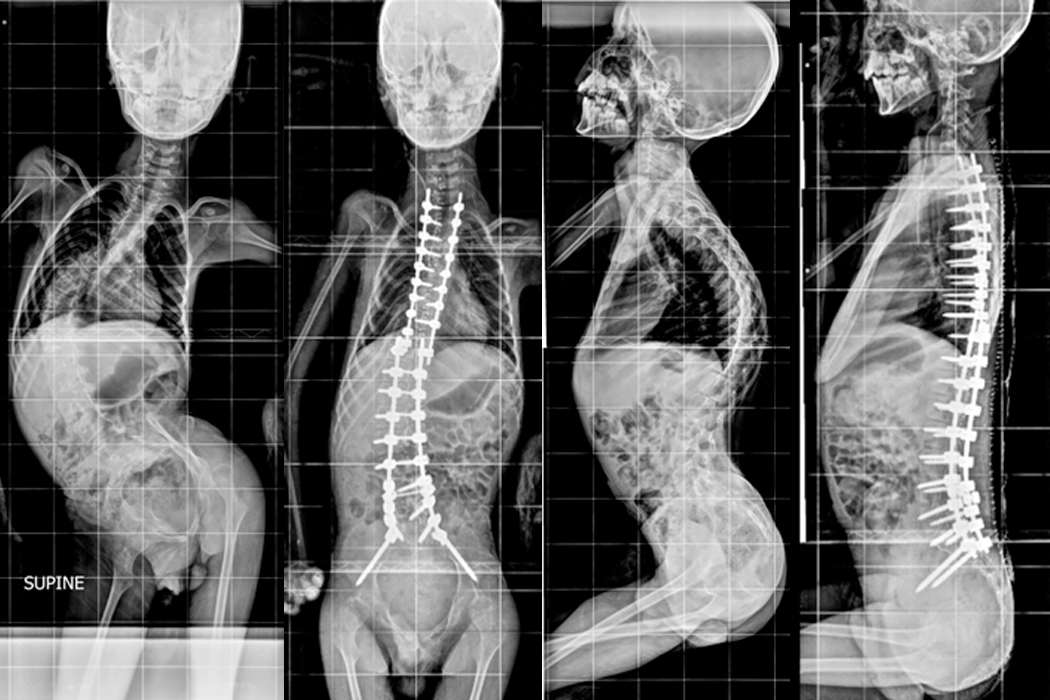

Patient A

In the year 2017 a 12 year old school girl presented with severe deformity over the back noticed 3 years ago. She underwent Anterior and Posterior Scoliosis correction.